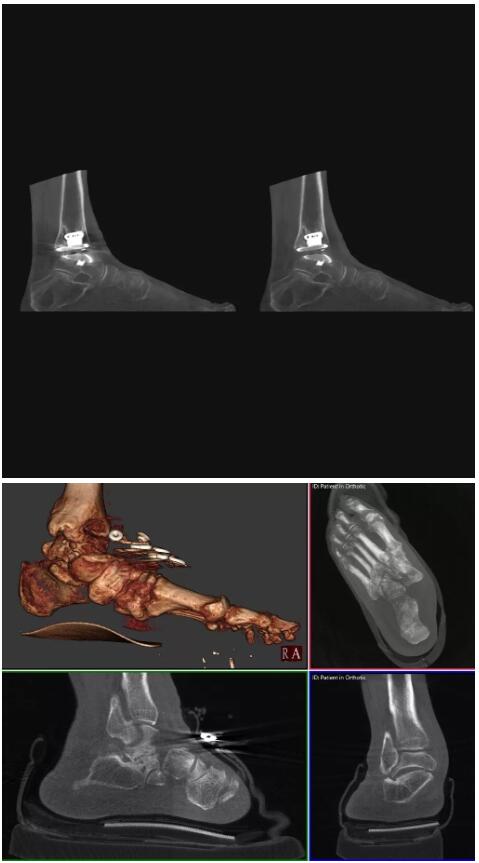

以下是這些“特立獨行”的CT所拍出來的圖像: